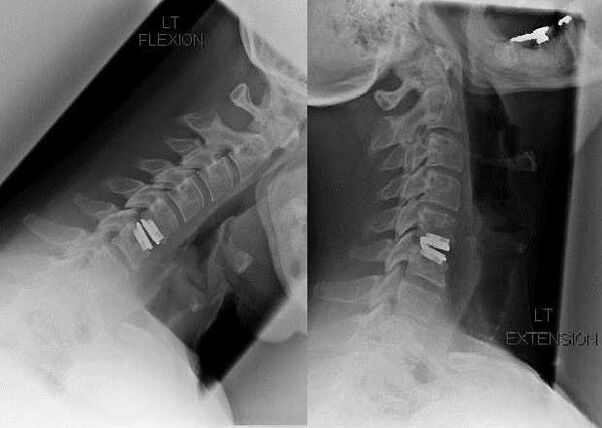

Intervention chirurgicale

Les indications d'une intervention chirurgicale comprennent l'inefficacité du traitement conservateur et les complications de l'ostéochondrose cervicale, par exemple la myélopathie discogène, le syndrome de l'artère vertébrale et le syndrome radiculaire. Pour soulager la charge sur la moelle épinière, les vaisseaux sanguins et les racines vertébrales, les opérations suivantes sont effectuées :

Au cours de l’intervention chirurgicale, des fragments osseux et des ligaments peuvent être excisés et les disques intervertébraux peuvent être retirés en totalité ou en partie. Pour les petites protubérances herniaires, une vaporisation laser du noyau du disque est souvent réalisée.

Après l'ablation des structures vertébrales, la stabilisation des segments mobiles de la colonne vertébrale par fusion vertébrale ou par l'installation d'autogreffes osseuses et cutanées est souvent nécessaire.